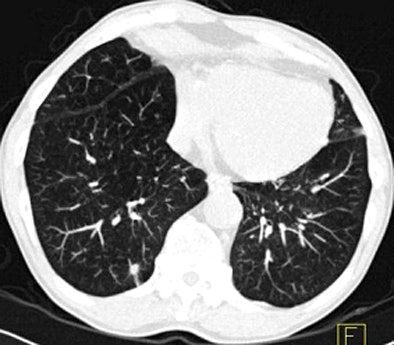

![]() |

| Images above and below show a spiculated nodule measuring 169 mm3 at baseline low-dose CT screening. Bottom image, acquired four years after the baseline scan, shows that the nodule has resolved. All images courtesy of Dr. Rosemarijn Vliegenthart. |